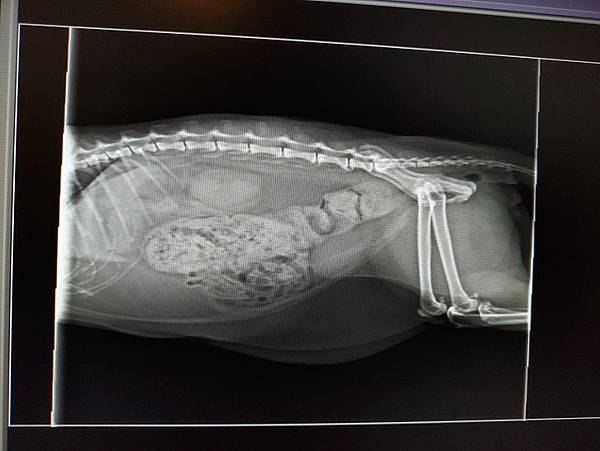

摸肚子感覺有硬便,但因為肥肉太多無法確定,決定拍X光和驗血

拍了X光側照一張,很多便便且看起來後端較硬